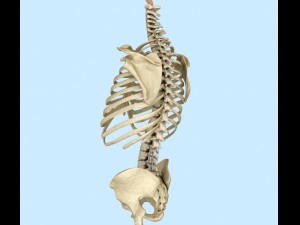

spinal fixation system - titanium bracket 3D 모델

spinal fixation system - titanium bracket. human spine, spinal cord, sacrum and fixation system medically accurate high quality 3d model.

hi-poly 3d model of human spine with internal structure.